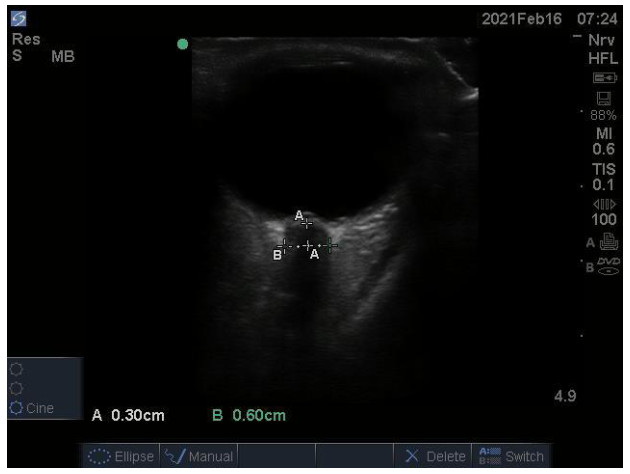

患者于术后12 h使用便携式彩色超声诊断仪M-Turbo(FUJIFILM SonoSite,博塞尔市,美国)测量ONSD。超声测量时,患者取仰卧位,透明敷贴保护双眼,头居中,使用高频(6~13 MHz)线阵探头,涂抹凝胶后,将探头轻放于患者闭合的眼睑上,对眼球后方3 mm处的视神经鞘进行测量,双眼扫描方向包括横断面和矢状面,各进行3次扫描,取平均数,精确至0.1 mm。ONSD测量由同一名经过床旁超声测量ONSD培训的重症医学科医生完成。见图 1

图 1 超声测量视神经鞘直径示意图 Fig 1 Ultrasound measurement of optic nerve sheath diameter